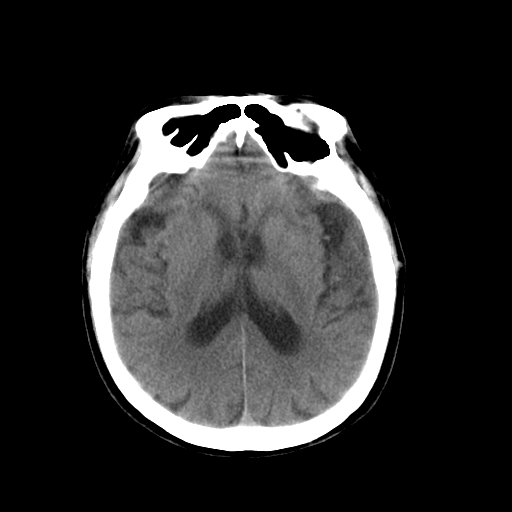

以下是引用dsl555在2008-11-11 18:52:00的发言:[br]四脑室后上方,四叠体池上方可见一小结节状稍高等密度影,比40天略大,建议mri或增强

以下是引用zjzjr在2008-11-12 8:28:00的发言:[br]四脑室后方略高密度影,周围环一低密度水肿带,四脑室受压变形,考虑小脑蚓部血肿吸收期或占位,建议增强